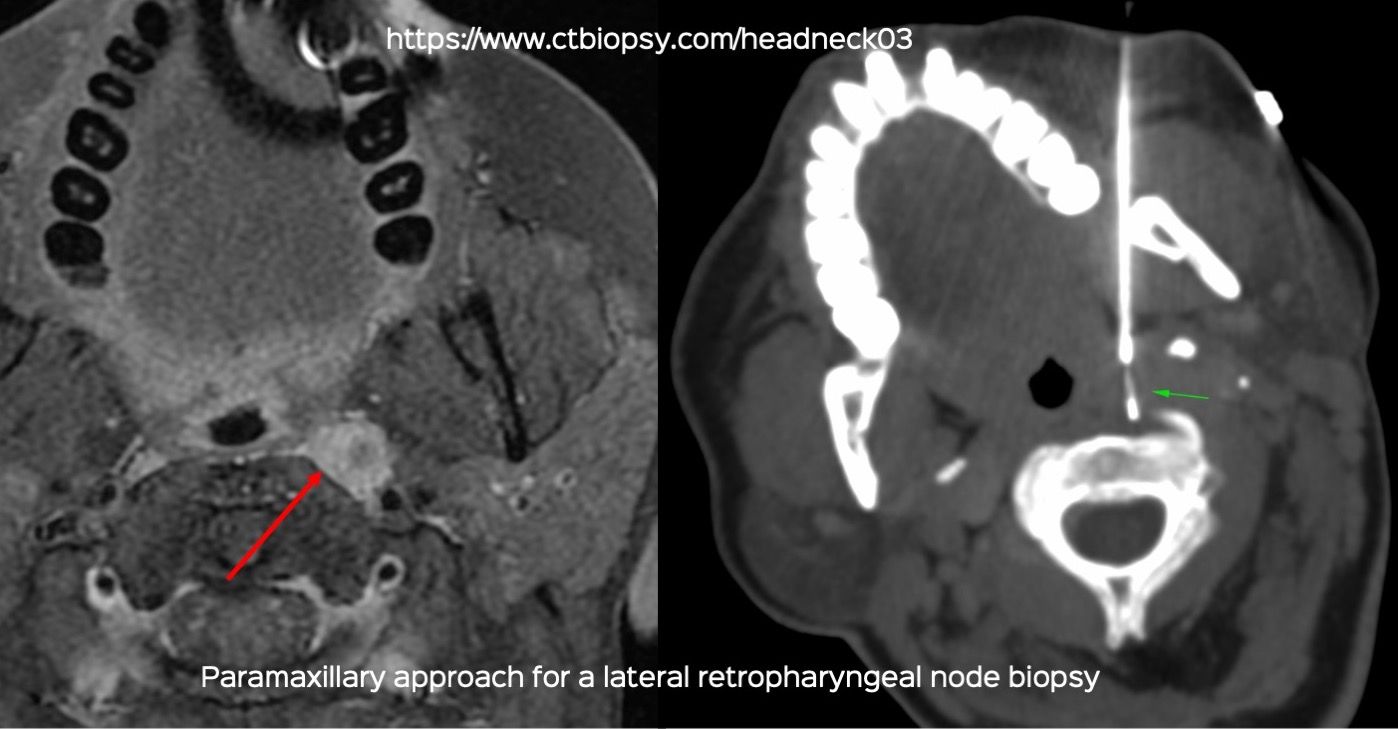

Case 78: Lateral Pharyngeal / Retropharyngeal Lesion Biopsy with a Paramaxillary Approach